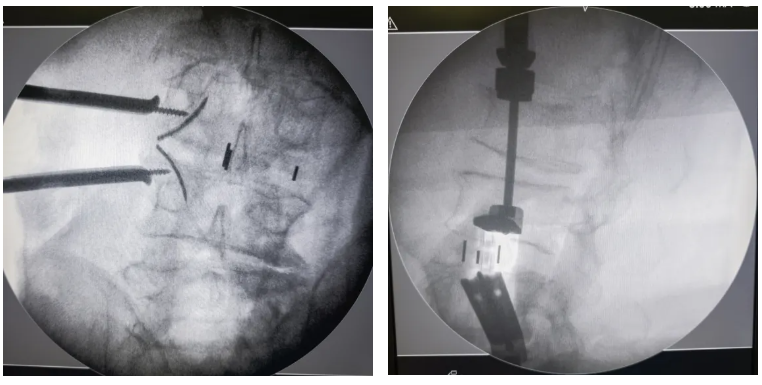

術中(zhong)影(ying)像

固定夾(jia)開(kai)路器(qi)開(kai)路并確(que)認植入(ru)安全性(xing)——

①椎體邊緣骨贅較多時,使用(yong)開路器(qi)確認(ren)固定夾假體實際植入時的安全性,防止固定夾假體打到椎體之外(wai)

②固定夾(jia)開路(lu)器優(you)先打向椎體邊緣(yuan)骨贅較多一側

③椎體(ti)邊緣骨(gu)贅不明顯(xian)時(shi),可選擇性使用固定夾(jia)開路(lu)器

透視確認手術節段——

手術工具展(zhan)示——